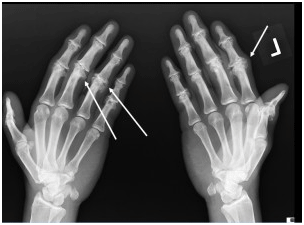

ΕΙΚΟΝΑ 1b. Εκτεταμένη οστεοφύτωση σε ασθενή με ΔΟΑ

Στη διαβρωτική ΟΑ το υπερηχογράφημα υψηλής ευκρίνειας δείχνει τις κεντρικές διαβρώσεις και τα οστεόφυτα, την πάχυνση του αρθρικού υμένα, συλλογή υγρού και τενοντοελυτρίτιδα (Grassi et al, 2000; Iagnocco et al, 2005; Vlychou et al, 2009).